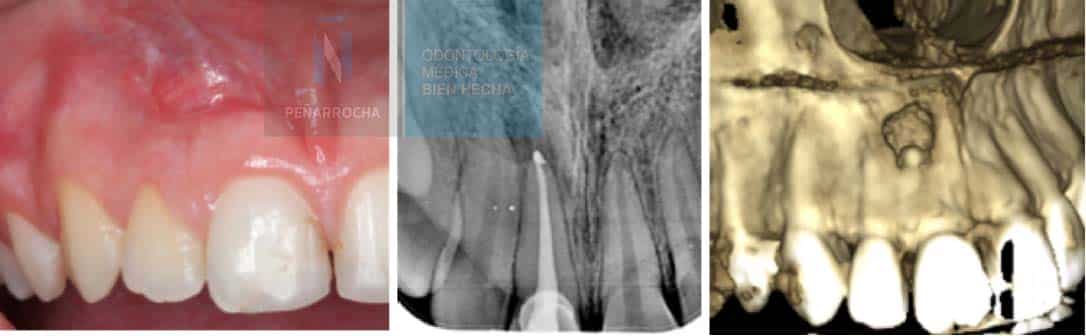

These lesions may come and go intermittently. Without proper treatment, the infection can spread to the surrounding bone or soft tissues. A clinical exam combined with X-rays or CBCT imaging is needed for a definitive diagnosis.

X-ray signs of a failed root canal treatment

One of the most reliable diagnostic tools for detecting root canal failure is dental radiography. With X-rays, the specialist can carefully examine the inside of the tooth and root canals to determine whether the treatment has been successful or if signs of failure are present.

Some of the most common radiographic signs of a failed root canal treatment include:

- Unfilled canals: an X-ray may reveal empty spaces along or at the end of the root canal that were not properly sealed. These gaps provide an entry point for bacteria, increasing the risk of infection and reinfection.

- Overfilling: when the filling material extends beyond the root apex, it can irritate the surrounding periapical tissues. On the radiograph, this appears as a white extension beyond the tip of the root.

- Dark areas around the root: dark or radiolucent zones in the bone surrounding the root are often a sign of infection or periapical lesions that compromise the bone structure.

- Periapical lesions: visible as darker or radiolucent areas around the tooth apex, periapical lesions indicate the presence of persistent inflammation or an active infection.

- Untreated canals: sometimes additional canals are missed during treatment. On an X-ray, they appear as radiolucent areas since they were not cleaned, shaped, or filled. Their presence can cause ongoing infection and treatment failure.

- Root fractures: although difficult to detect, root fractures may appear as fine, dark lines along the root. They can also cause irregular changes in the surrounding bone pattern, suggesting structural compromise.

In some cases, X-rays may show a radiolucent lesion around the apex of a tooth, even when the root canal appears to have been performed correctly. This suggests that, despite proper technique, the treatment has ultimately failed. A follow-up radiograph after apical surgery can often confirm the healing of the affected area.

In any situation, it is essential that an endodontist or oral surgeon evaluates the radiograph to accurately determine the condition of the tooth and whether additional treatment is required.

The first step is to schedule an appointment with an experienced endodontist or oral surgeon to evaluate your situation. They can perform a clinical examination, X-rays, and CBCT scans to determine the cause of the failure and study your case in depth.

During the consultation, the specialist will assess your symptoms, review radiographic images, and determine whether the previous treatment was insufficient, if there is a persistent infection, or if another issue is present.

Diagnosing a failed root canal requires a detailed evaluation by a dental professional. The dentist will assess your symptoms and use X-rays and CBCT imaging to examine the tooth and surrounding tissues. This allows them to determine if there is an infection or if the canal filling is inadequate.